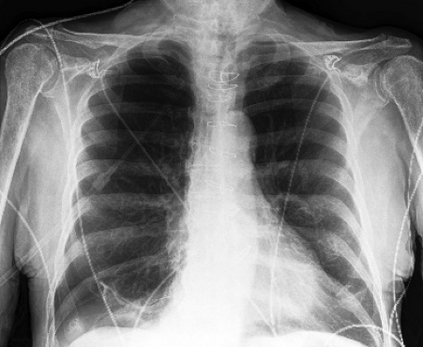

The availability of large public datasets and the increased amount of computing power have shifted the interest of the medical community to high-performance algorithms. However, little attention is paid to the quality of the data and their annotations. High performance on benchmark datasets may be reported without considering possible shortcuts or artifacts in the data, besides, models are not tested on subpopulation groups. With this work, we aim to raise awareness about shortcuts problems. We validate previous findings, and present a case study on chest X-rays using two publicly available datasets. We share annotations for a subset of pneumothorax images with drains. We conclude with general recommendations for medical image classification.